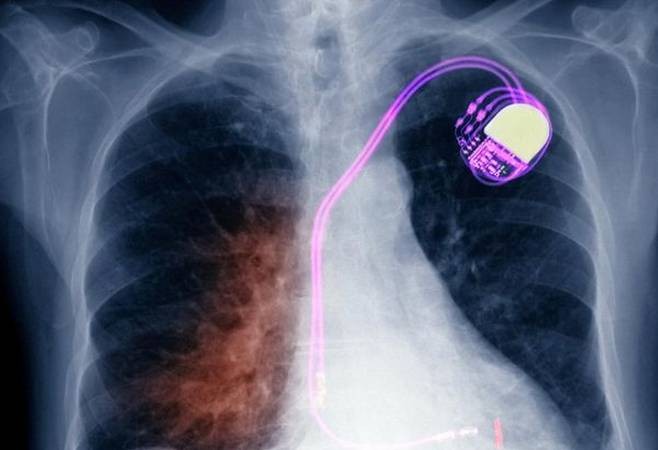

心脏X线片